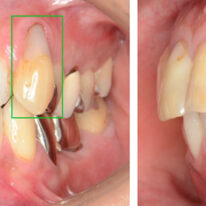

実際のお口の中を見てください

上顎

すでに抜歯された部分には隣の歯が移動して狭くなっています。根が残っている第一大臼歯は赤く炎症になっています。

下顎

左側第一大臼歯の抜歯部位の骨が痩せて狭くなっています。右側は内側の歯が半分割れています。

その後方に位置する親知らずは横に寝ていてわずかに顔が出ています。